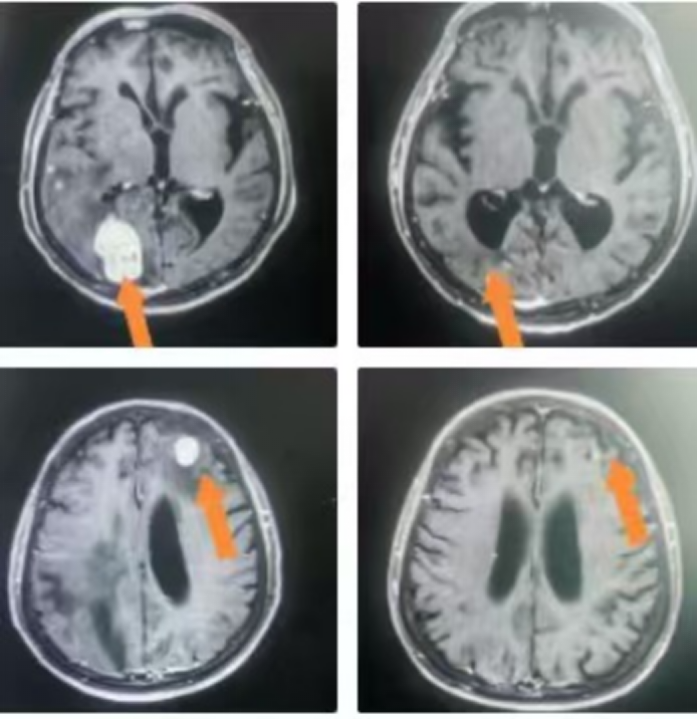

△病例展示

2. 晶格放疗(Lattice Radiation Therapy, LRT):这是GRID疗法的3D进化版。我们在CT模拟定位后,基于患者的个体化肿瘤三维形貌,在治疗计划系统中虚拟设计一个三维的“剂量晶格”,将多个高剂量“球体”精确布设在肿瘤内部,特别是乏氧和增殖活跃的区域。这种“多点聚焦”式的设计,实现了治疗计划的高度个体化、精确化与安全化。

1. 卓越的局部控制率: 对于大体积肿瘤,SFRT展现了惊人的快速消退能力。患者通常在治疗后短期内即可观察到肿瘤体积的显著缩小,症状(如疼痛、压迫)得到迅速缓解。